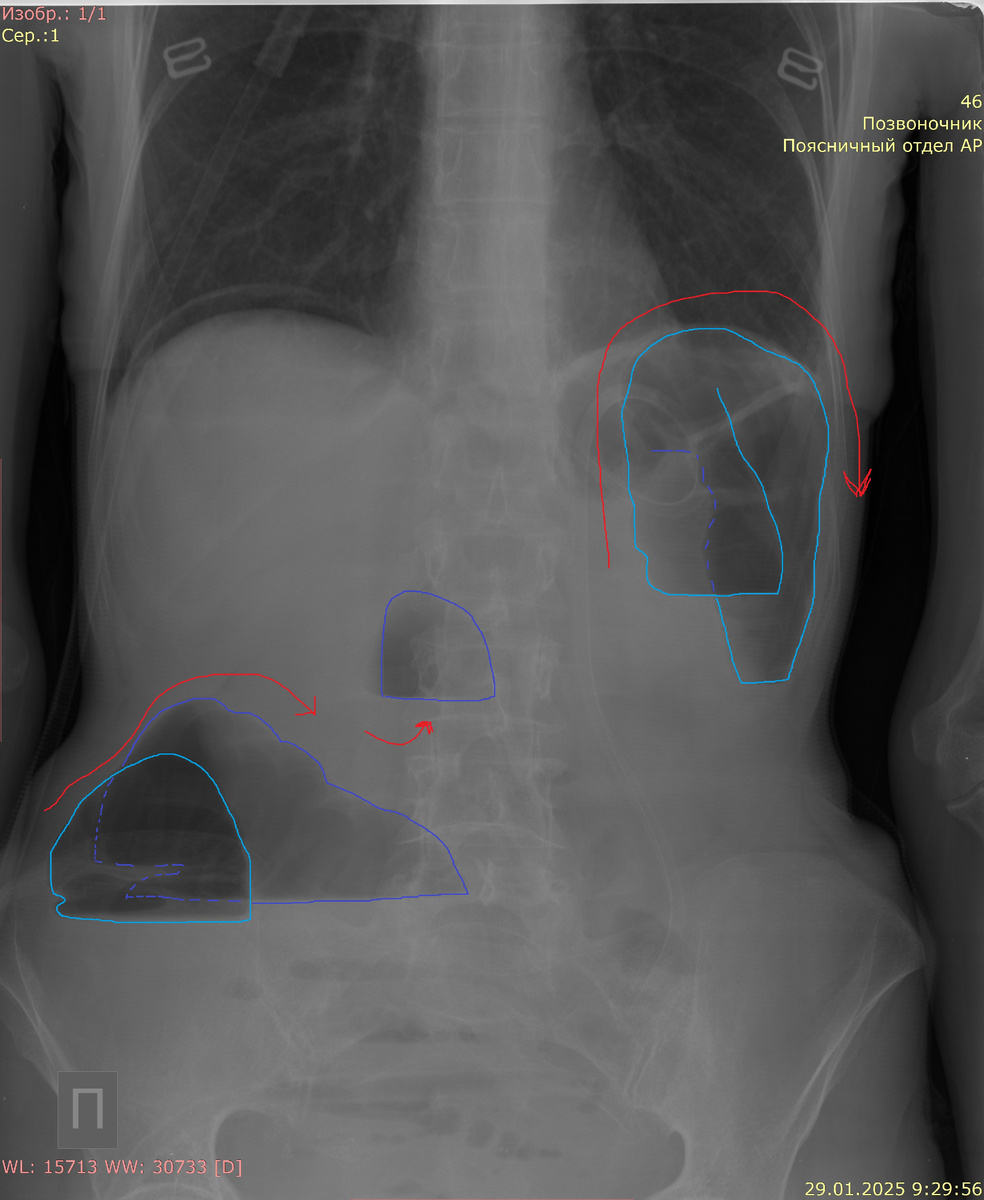

Синим показана кишка. В печеночном углу уровень "жидкость-газ". В селезеночном - арка. Стрелками указано направление кишки.

На рентгенограммах специалисты могут заметить общие признаки, такие как расширение дистальных отделов кишки и сужение или отсутствие контрастирования в более проксимальных участках. Эти находки позволяют врачам оценить уровень непроходимости и выявить потенциальные причины ее возникновения.

Ширина толстой кишки боле 60 мм - непроходимость.